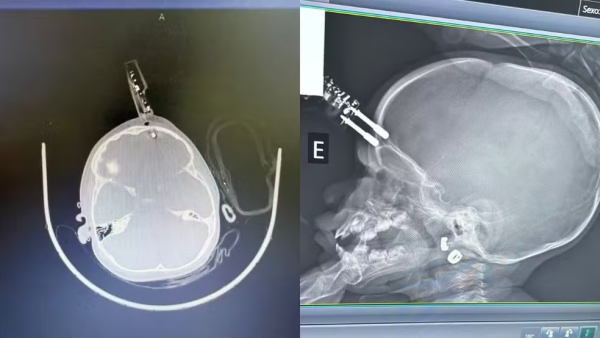

Uma menina de 1 ano foi submetida a uma cirurgia de urgência após cair da cama e ficar com um carregador de celular cravado na testa, em Divinópolis, no Centro-Oeste de Minas Gerais. O acidente ocorreu na última terça-feira 13.

A principal hipótese é que a menina estivesse segurando o carregador no instante da queda. O objeto acabou atingindo a região frontal do crânio, próximo ao olho, e perfurou o osso, alcançando o tecido cerebral.

O neurocirurgião Bruno Castro informou que a mãe da criança teria se ausentado brevemente para ir ao banheiro quando o acidente aconteceu. A menina foi levada imediatamente ao bloco cirúrgico, onde passou por procedimentos de limpeza da área atingida, retirada do objeto, lavagem, fechamento e reconstrução do local lesionado.

Segundo o especialista, a intervenção rápida foi fundamental para evitar complicações mais graves, como hemorragias ou infecções severas. A criança recebe antibióticos de forma preventiva, conforme o protocolo médico, e segue sob monitoramento hospitalar.